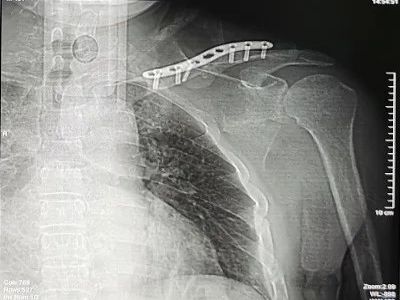

因患者左肩关节疼痛伴活动障碍,行“左锁骨骨折切复内固定术”。